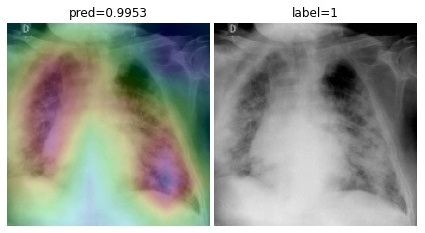

To overcome the aforementioned issues and force the model’s attention to the correct regions of interest (ROIs), we introduce the COVID-CXNet. Our model is initialized with the pretrained weights from CheXNet. A dataset of 3,628 images, 3,200 normal CXRs and 428 COVID-19 CXRs, are divided into 80% as training-set and 20% as test-set. Batch size is set to 16, rather than 32 in previous models, regarding memory constraints. Grad-CAMs of the COVID-CXNet for random images are plotted in Fig. 15.

Refer to caption

Figure 15: Grad-CAM visualization of the proposed model over sample cases

More Grad-CAMs are available in Appendix A. Heatmaps are more accurate than previous models, while an accuracy of 99.04% and an f-score of 0.96 are achieved. Table 3 is the confusion matrix of the proposed model.